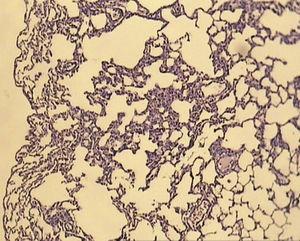

ResultsAll of the rats survived until the end of the study period. Data belonging to histological changes from lung samples after reperfusion are represented in Table 1. In the ischemia–reperfusion group, tissues showed histological changes with partial destruction of pulmonary architecture, neutrophilic infiltration, intra-alveolar hemorrhage and edema (Figure 1). Grades 1, 2 and 3 of lesions were obtained in the ischemia–reperfusion group, with an average of 2.3. These pathological changes in the ischemia–reperfusion + melatonin group, particularly neutrophilic infiltration and edema, were much less than in the ischemia–reperfusion group (Figure 2). Four animals in the ischemia–reperfusion + melatonin group presented no injury and the others had lesions grades 1 and 2, averaging 0.7. Histopathologically, there was a significant difference (P = 0.001) between the two groups. The average of histological changes in the sham group (0.2) was lower than the ischemia–reperfusion + melatonin group, but with no statistical significance (Figure 3).

Figure 1. Light microscopic view of lung tissues from ischemia–reperfusion group. Extensive histological changes with inflammatory cell infiltration and partial destruction of lung architecture (magnification of 10 × 10, H&E staining).

Figure 2. Light microscopic view of lung tissues from ischemia–reperfusion + melatonin group. More preservation of nearly normal structure (magnification of 10 × 10, H&E staining).

Figure 3. Representative photomicrograph of lung tissues in the sham group showing normal structure (magnification of 10 × 10, H&E staining).